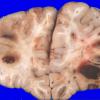

NEOPLASMS (HEMATOLYMPHOID)

Granulocytic Sarcoma (3)